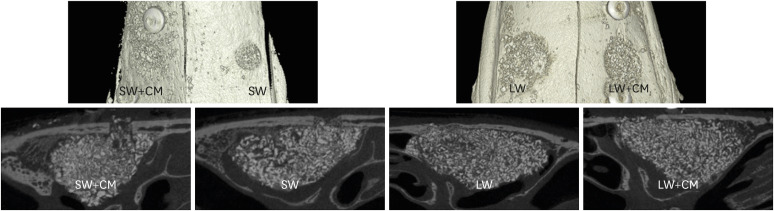

Methods: Small bony access windows (SW; ø 2.8 mm) were made in 6 rabbits and large windows (LW; ø 6 mm) in 6 other rabbits. Both sinuses in each rabbit were allocated to groups with or without coverage of a collagen membrane (CM) on the window, resulting in 4 groups: SW, LW, SW+CM, and LW+CM. After 4 weeks of healing, micro-computed tomographic, histologic, and histomorphometric analyses were performed.

Results: Bony healing in the window area was incomplete in all groups, but most bone graft particles were well confined in the augmented cavity. Histologically, the pattern of new bone formation was similar in all groups. Histomorphometrically, the percentage of newly formed bone was greater in the groups with CM than in the groups without CM, and in the groups with SW than in the groups with LW (12.92%±6.40% in the SW+CM group, 4.21%±7.73% in the SW group, 10.45%±4.81% in the LW+CM group, 11.77%±3.83% in the LW group). The above differences were not statistically significant (P>0.05).